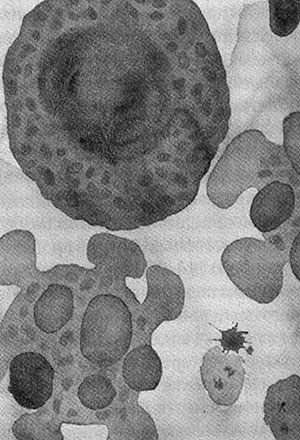

Когда клетки тела изнашиваются или повреждаются, они погибают в результате насильственного самоубийства — апоптоза. Клетка распадается на части, они упаковываются и перевариваются. Нарушение механизмов апоптоза приводит к раку — конфликту интересов отдельных клеток и организма в целом. Видимо, апоптоз необходим для обеспечения целостности многоклеточных организмов, но почему независимые клетки согласились на гибель ради высшего блага? Сегодня апоптоз контролируется митохондриями, которые унаследовали машину смерти от своих предков-бактерий. Так неужели целостность индивидуума действительно родилась в борьбе не на жизнь, а на смерть?

Смерть от апоптоза: жить клетке или погибнуть, решают митохондрии